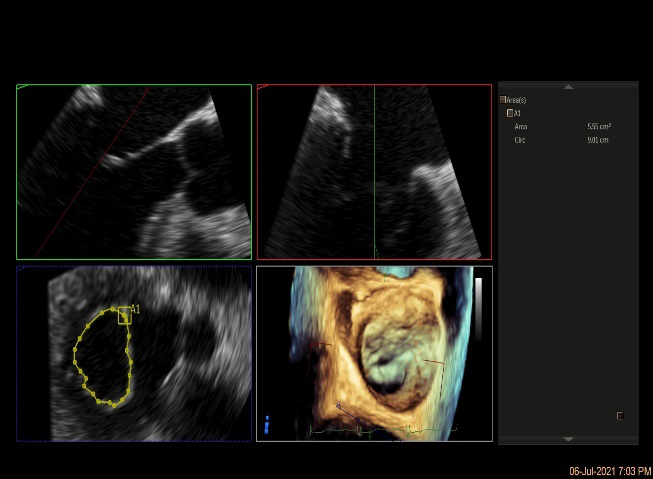

3D MV View

3D-color MV view:血流主要来源于2区近3区

Qlab软件勾画估测瓣口面积约:6.16cm²

二尖瓣口平均跨瓣压差:1mmHg

3D视图下观察二尖瓣双孔形态

3D-color:残余少量返流